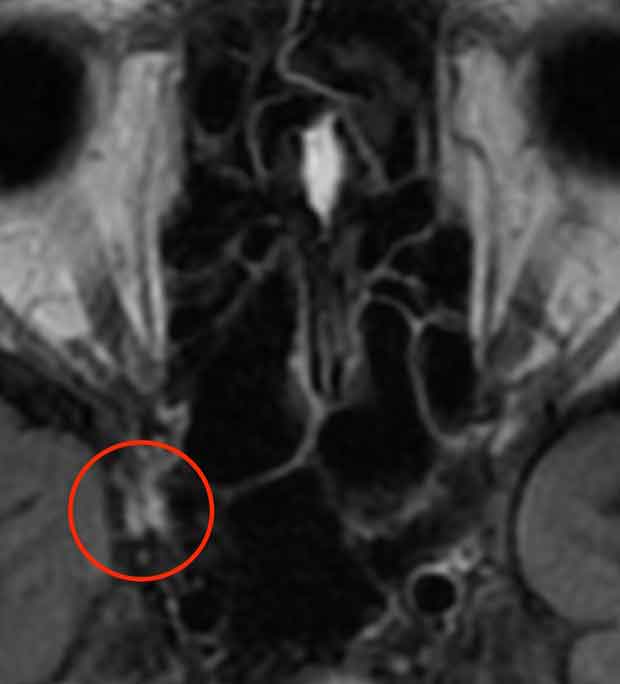

40代女性の例:右目の痛みと複視で受診。MRI検査でTolosa-Hunt症候群と診断し、ステロイド治療で改善。

右の海綿静脈洞の部分に白く写る炎症部分があり、Tolosa-Hunt症候群と診断。